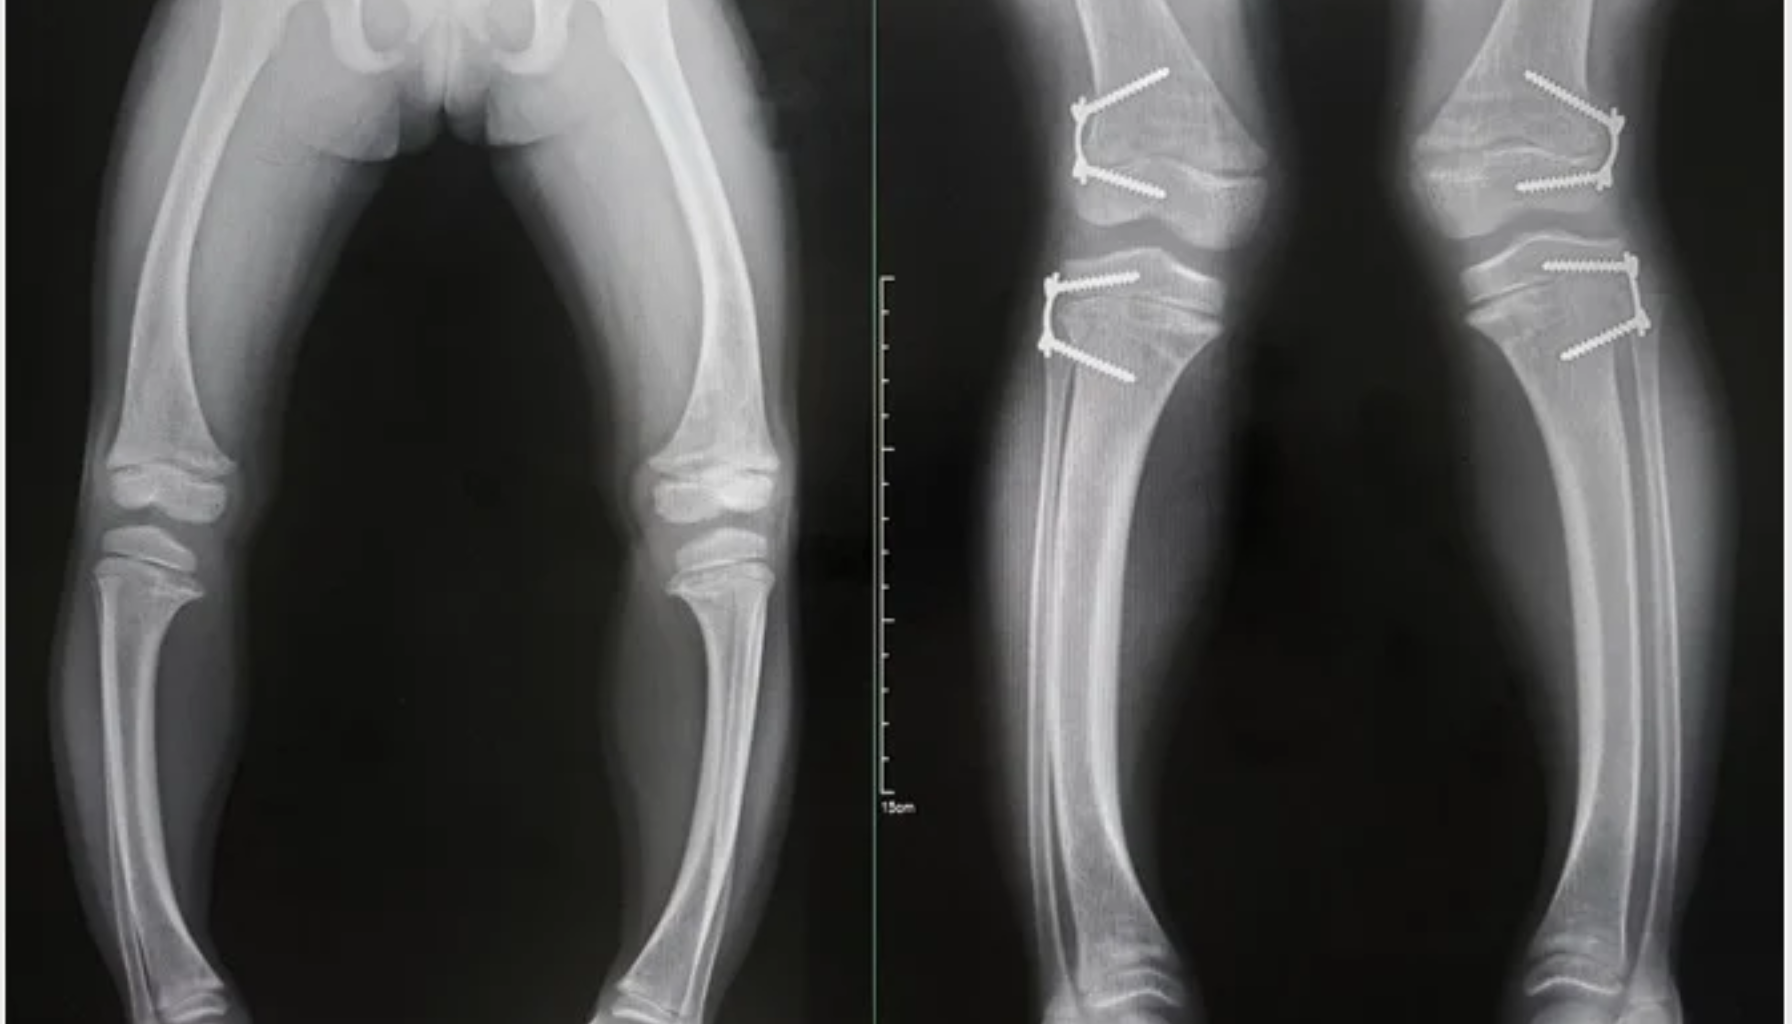

Symptomene på rakitt kan variere, men de mest tydelige tegnene er relatert til barnets skjelett og vekst. Barn med rakitt får ofte myke og svake bein som kan bøye seg, noe som kan gi hjulbeint eller kalvbent utseende. De kan også oppleve forsinket vekst, smerter i bein og muskler, samt hyppige brudd. Hos spedbarn kan rakitt vise seg ved forsinket lukking av fontaneller, uvanlig hodeform eller problemer med tenner som bryter frem sent og lett får hull.

Mange foreldre legger også merke til generell slapphet, irritabilitet og nedsatt motorisk utvikling. I noen tilfeller kan brystkassen og bekkenet utvikle unormale former. Symptomene kan være diffuse i starten, men blir mer alvorlige dersom tilstanden ikke oppdages tidlig. Ved mistanke er det derfor viktig å kontakte lege, som kan stille diagnose gjennom blodprøver og røntgen. Tidlig behandling kan hindre varige skader på skjelettet.

Behandlingen av rakitt tar utgangspunkt i å korrigere mangelen på D-vitamin, kalsium og fosfat. Vanligvis får barnet tilskudd av D-vitamin i form av dråper eller tabletter, kombinert med et kosthold rikt på melk, fet fisk og berikede matvarer. Dersom sykdommen har ført til alvorlige skjelettforandringer, kan barnet også trenge fysioterapi eller i sjeldne tilfeller kirurgisk behandling for å rette opp deformiteter. Forebygging er likevel det viktigste verktøyet. Helsedirektoratet anbefaler at alle spedbarn får daglig D-vitamintilskudd fra fire ukers alder.